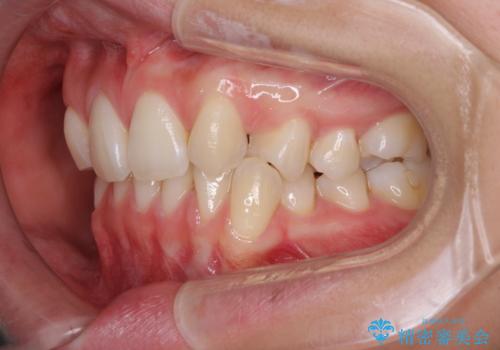

上顎前歯が2本欠損 インビザラインによる叢生の解消

- 深い咬み合わせと前歯のデコボコを気にして来院された患者様です。

上顎前歯2本が欠損しているため、妥協的なゴールを設定しインビザラインで矯正治療を行うこととしました。

上下前歯の大きさのアンバランスにより、深い咬み合わせと奥歯の咬みにくさがなかなか解決されず、治療に長期間を要することとなりました。